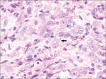

Inflammatory myofibroblastic tumor (IMT) is a rare tumor of uncertain origin with variable biological behavior ranging from reactive lesions to highly aggressive malignancy. Oral IMTs are extremely rare and only 25 cases had been reported so far. A case of IMT with sarcomatous transformation in an extraction site with a history of tooth extraction following tooth mobility of an upper left molar tooth is presented here. The tooth was extracted following a complaint of gingival swelling and mobility of tooth. Though malignant transformation in IMTs had been documented in the extra oral sites, wide search of associated literature suggests, this is the first case of oral IMT showing malignant change associated with gingiva. The case report attempts to highlight the variant possibilities of tooth mobility other than periodontitis and the importance of assessing the primary cause of such conditions.